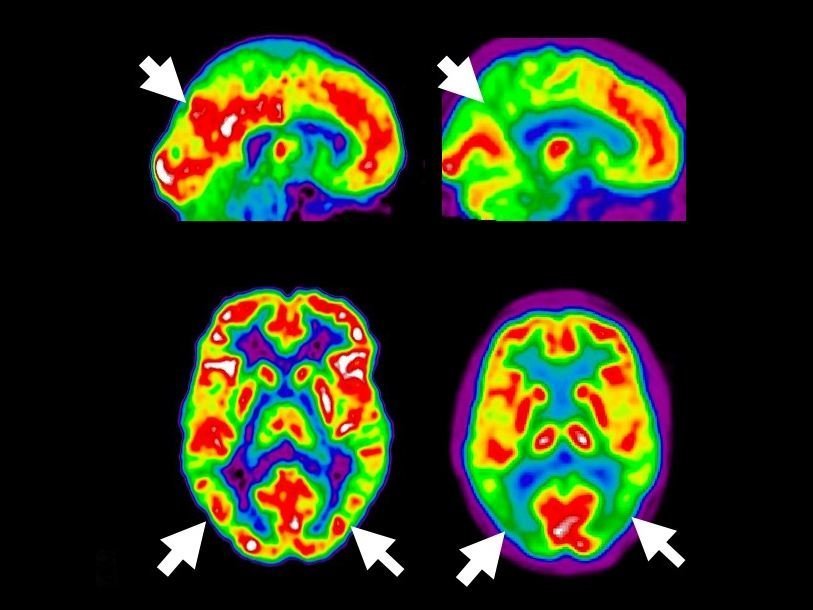

Интеллектуальный партнер проекта Исследования, проведенные в Техническом университете Чалмерса (Chalmers University of Technology, Швеция) и Вроцлавском политехническом университете (Wroclaw University of Technology, Польша), показали возможность уничтожения белков, ответственных за болезнь Альцгеймера, Паркинсона и Крейтцфельда-Якоба (также известную как коровье бешенство) при помощи лазера. Результаты исследований опубликованы в журнале Nature, кратко с содержанием работы можно познакомиться на сайте польского университета.

Ученые разработали мультифотонную лазерную установку, которая позволяет отличать токсичные (амилоидные) белки от здоровых, и уничтожать их. До этого, по словам руководителя исследования Петра Ханчица (Piotr Hanczyc), для лечения подобных заболеваний лазерное излучение не использовалось. Сейчас амилоидные белки уничтожают при помощи химиотерапии.